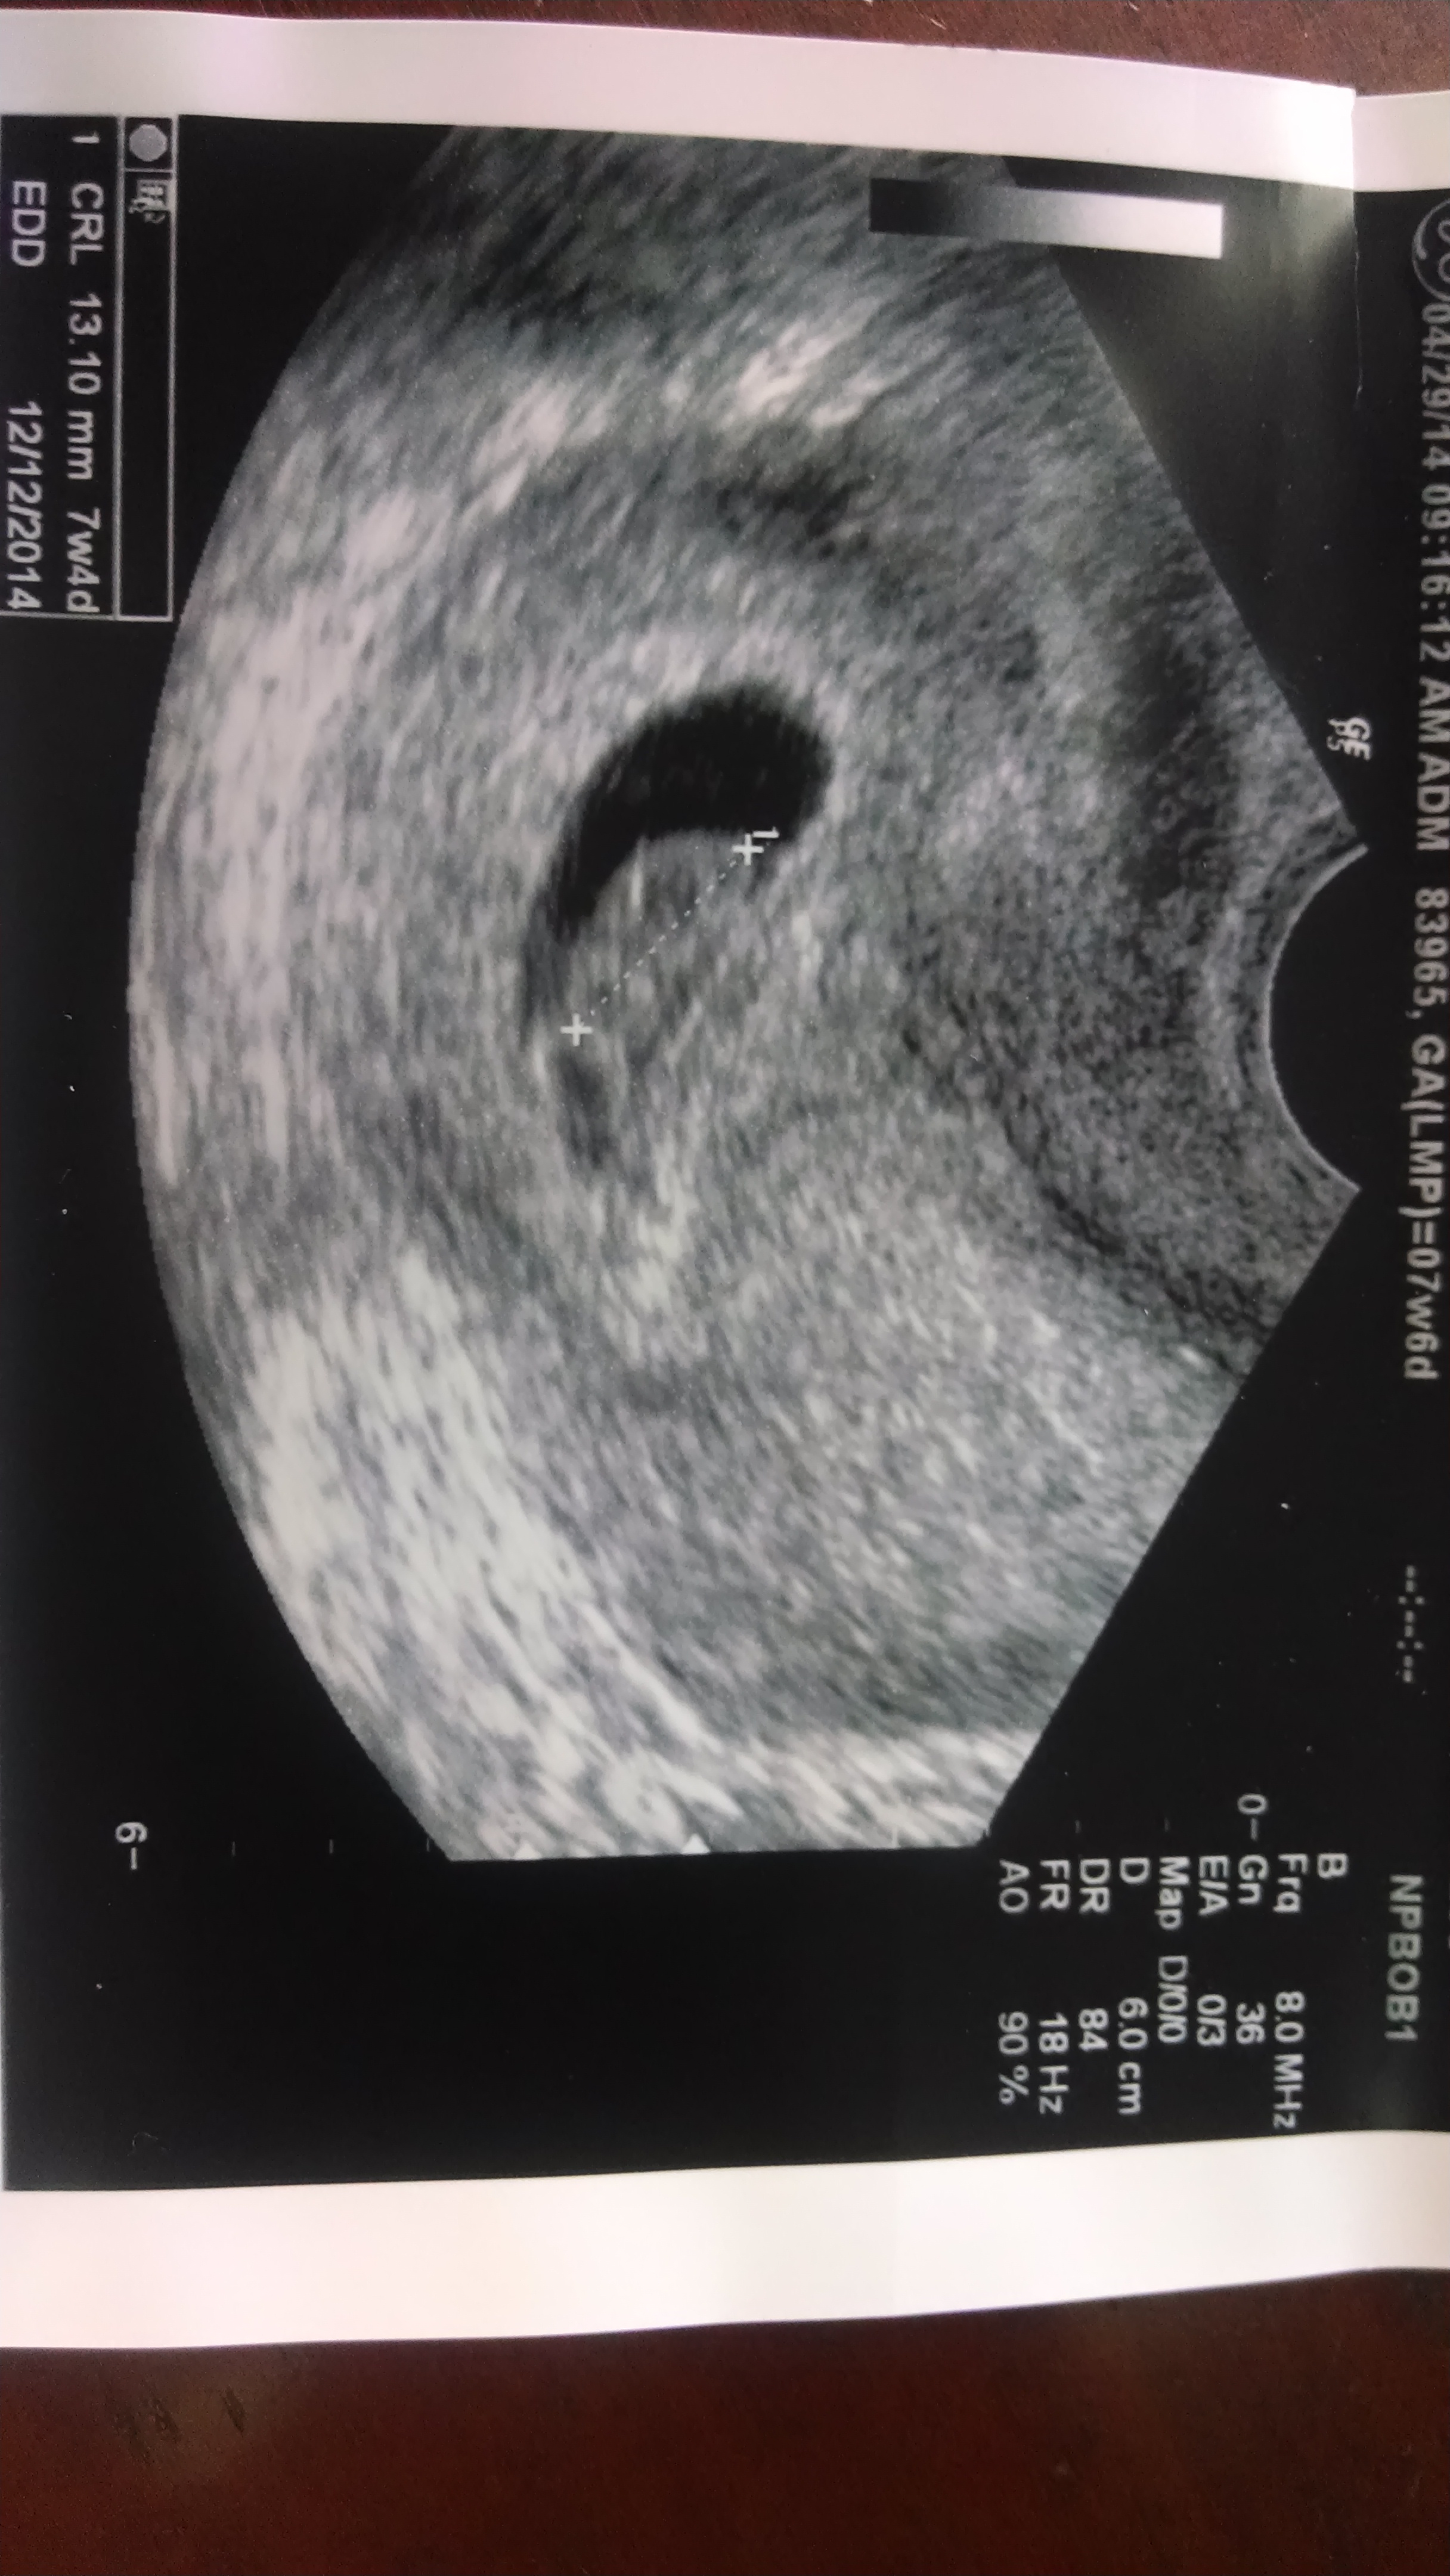

FET #1 December 2014